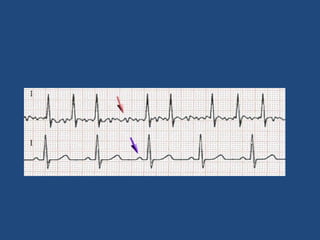

Mobitz Type 1

• Progressive prolongation of PR interval.

• Atrial impulse (P waves) may not be conducted

through AVN and gets blocked and hence no

QRS.

• No clinical significance unless symptomatic.

Mobitz Type 2

• Non prolongation and fixed PR interval.

• Non conducted p waves

• No ventricular activity -Drop beats / No QRS

Most times Infranodal